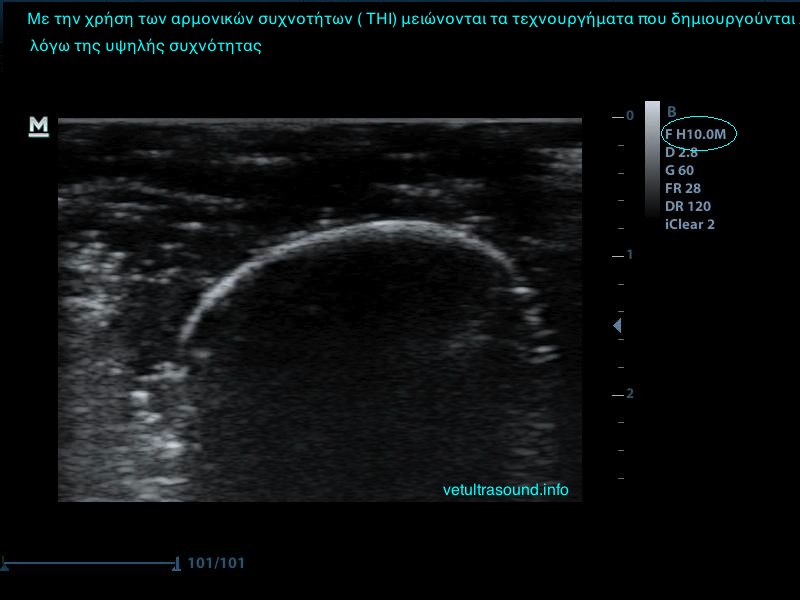

3) Τη συχνότητα, δηλαδή όσο πιο μεγάλη είναι αυτή, τόσο πιο πολλές λεπτομέρειες βλέπουμε αλλά ταυτόχρονα αυξάνονται τα τεχνουργήματα από αέρα και άλλες δομές. Οι αρμονικές βοηθούν στην καταστολή αυτών των τεχνουργημάτων.